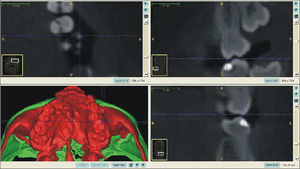

O surgimento e o aumento da acessibilidade da TCFC agregaram uma maior credibilidade ao diagnóstico clínico e às investigações científicas no estudo das deformidades craniofaciais19. Todavia, as informações 3D fornecidas pelas TCFC ainda vêm sendo rotineiramente analisadas de forma 2D, por medidas lineares em cortes ortogonais5,20. A construção e sobreposição de modelos virtuais 3D ainda é uma metodologia pouco difundida. Este estudo é um dos pioneiros que utiliza este método para avaliação de ERM em pacientes com fenda. A sobreposição baseia‐se na construção dos modelos virtuais 3D, utilizando o software SLICER21, pelos arquivos obtidos na TCFC, seguida pela sua justaposição, que utiliza a base do crânio como referência e a final obtenção dos métodos de medidas intitulados: sobreposição por semitransparência e mapa por códigos de cores22. A sobreposição por semitransparência revela uma análise qualitativa, em que o momento pós‐tratamento é retratado por uma malha preta translúcida, sobre o modelo inicial em vermelho (figs. 9 e 10). O aparelho em leque demonstrou um deslocamento de quase todos os dentes para vestibular e uma movimentação vestíbulo‐posterior do segmento menor (lado esquerdo [fig. 9]). O mapa por códigos de cores permite um complemento da análise visual, sendo que cada cor reflete uma alteração na posição das estruturas: azul – recuo; verde – estabilidade e vermelho – expansão. A intensidade da cor está diretamente relacionada à quantidade de movimentação. Todo o mapa é seguido por uma escala, com os valores em milímetros para cada cor (figs. 11 e 12). A observação feita na sobreposição por semitransparência do expansor em leque é confirmada no mapa por código de cores e nas medidas lineares. Uma menor porção de vermelho é visualizada em molares, quando comparada aos pré‐molares. O deslocamento para posterior e vestibular do menor segmento é constatado pela presença de azul na mesial dos dentes e vermelho nas eminências alveolares do lado em questão. Diferentes tonalidades de azul são vistas na cervical dos incisivos, possivelmente uma retroinclinação em decorrência da ausência de apoio mecânico no local. Para a quantificação das mudanças no posicionamento dentário, primeiramente identificou‐se, nos 3 cortes ortogonais, os pontos de referência para a medida (ponta da cúspide mésio vestibular dos primeiros molares superiores e ponta da cúspide dos caninos), tanto do lado direito como do lado esquerdo, utilizando o software ITK Snap23. Os pontos foram marcados com uma esfera de 0,5mm de diâmetro, identificando a posição 3D destas referências no espaço (fig. 13). A aferição das distâncias Euclidianas entre as esferas foi realizada com o auxílio da ferramenta Q3DC no programa SLICER23. O paciente A obteve um aumento de 3mm na distância intercanina e de 6mm na distância intermolar. Na elucidação do paciente que utilizou o disjuntor mini‐Hyrax invertido com BTP (B), observa‐se na sobreposição por semitransparência um deslocamento vestibular, principalmente dos pré‐molares e uma constância das demais áreas, achados corroborados no mapa por código de cores. A área que não está verde é a região de pré‐molares, vermelho por vestibular e azul por palatino, notando uma tonalidade entre verde e vermelho (amarelo) no corpo da maxila do lado menor (esquerdo). A oclusal dos molares, em vermelho, representa a erupção dos elementos.